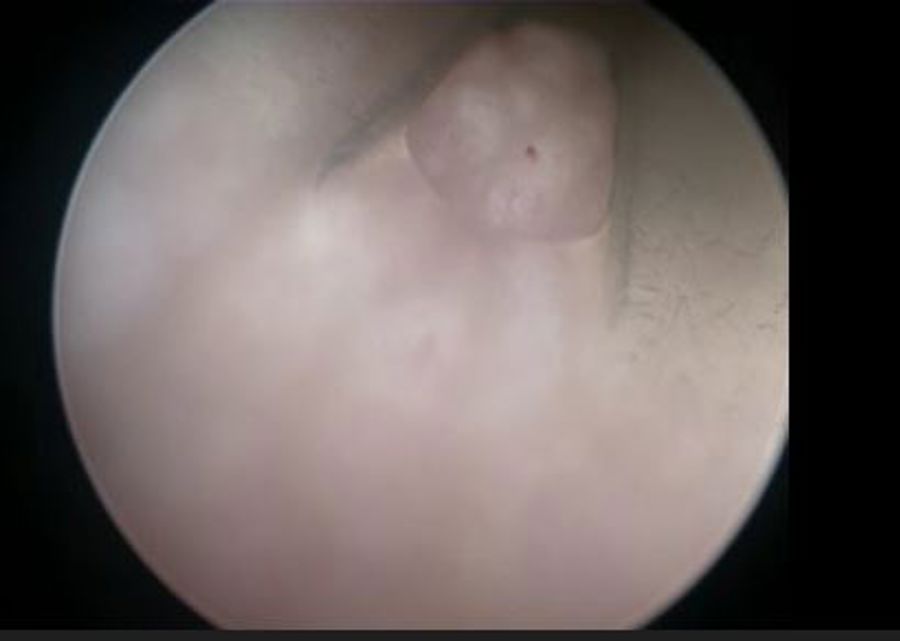

View from the inside of a Conventional Two-Eyelet Catheter

Draining of urine during catheterisation creates negative pressure inside the catheter. This causes the bladder mucosa to get sucked into the eyelets of the catheter, blocking them, leading to a urine flow stop.1

Repositioning of the catheter helps to release the mucosa and continue the draining of urine. Mucosal suction can cause microtrauma to the bladder wall and compromise the protective layer of the epithelial cells.1 A compromised bladder wall would give easier access for bacteria thus increasing the risk of UTIs.5,6